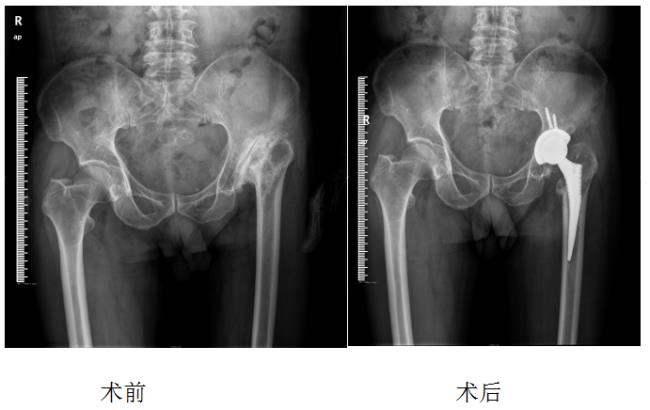

1、先天性髋关节发育不良:

术后5天基本恢复正常